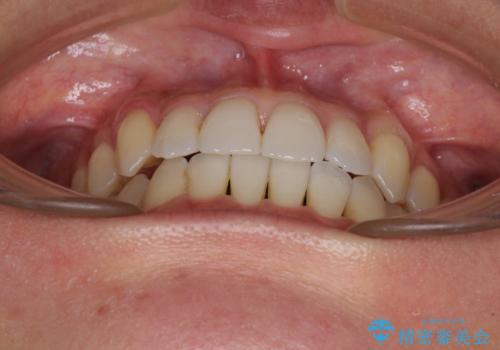

前歯のデコボコ インビザラインによる矯正治療

- 上下前歯の叢生と奥歯の反対咬合を気にして来院された患者様です。

インビザラインを用い、下顎はIPR(歯と歯の間を削る)と歯列全体を後方に移動させ、上顎は側方に拡大させることで歯列を改善していくこととしました。

骨格的に下顎が左側前方にずれているため、上下正中のズレや左右奥歯の咬み合わせを理想的な状態とすることは困難でした。